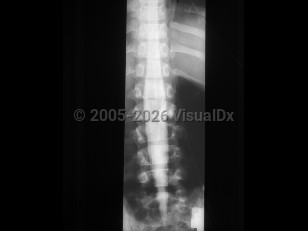

Osteoporotic vertebral compression fracture

Spondylolysis

Ankylosing spondylitis

Spondylolisthesis

Lumbar spinal stenosis

Tuberculous spondylitis

Adult spinal deformity